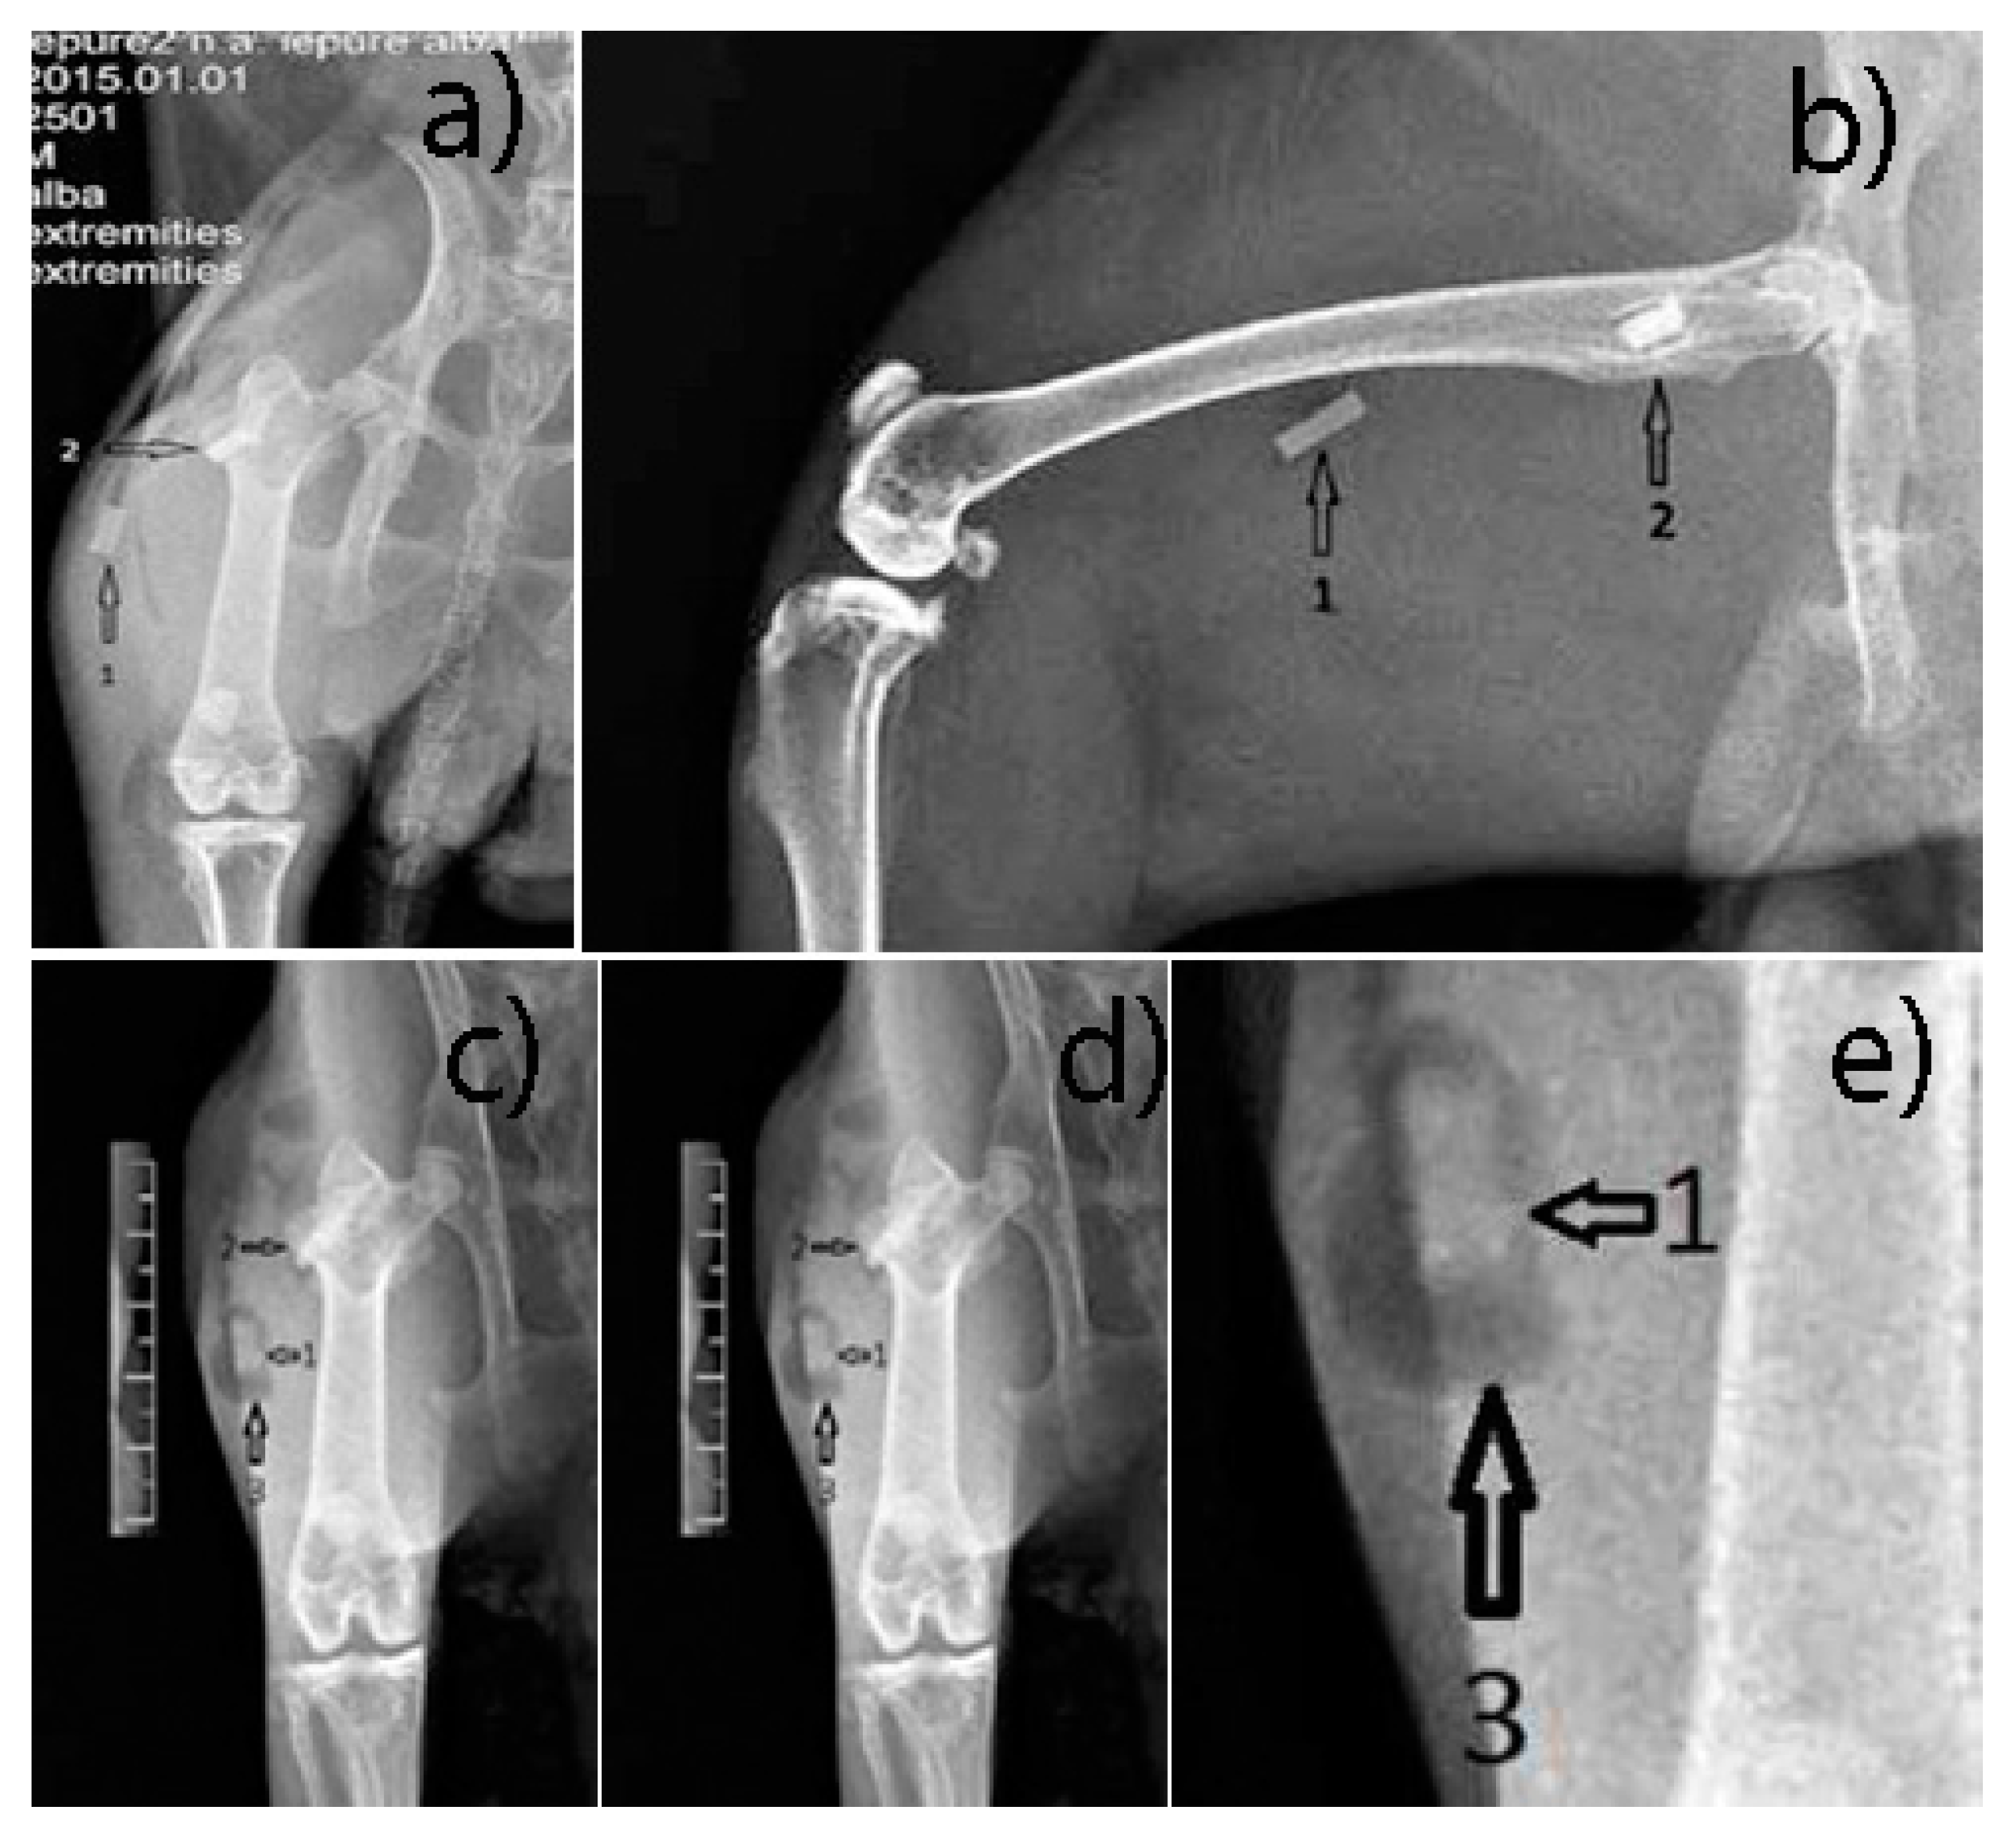

3.2.1. Radiological Follow-Up